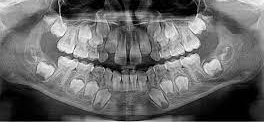

3. How old is the patient with the following X ray?